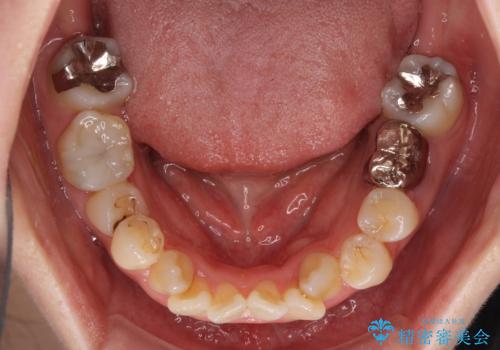

- 八重歯やデコボコを気にして来院された患者様です。

お住まいから船での通院となることから、補助装置を使用しながらインビザラインにて上下左右第一小臼歯4本を抜歯した矯正治療を行うこととしました。

ところが、インビザラインでの自己管理が煩わしいと感じてしまい、途中で矯正治療を投げ出すことになってしまいました。

相談の上、表側の目立ちにくいワイヤー装置により矯正治療を継続していくこととしました。